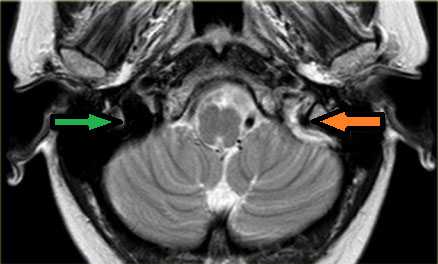

МРТ головного мозга: справа (зеленая стрелка) на Т2-взвешенном изображении отмечается имеющийся в норме феномен «пустоты потока» от правого сигмовидного синуса и яремной Вены. Слева (оранжевая стрелка) отмечается аномально высокий сигнал, в результате, вероятнее, тромбоза. Для подтверждения синус-тромбоза и окончательного определения локализации и протяженности тромбоза необходимо проведение МР-венографии.